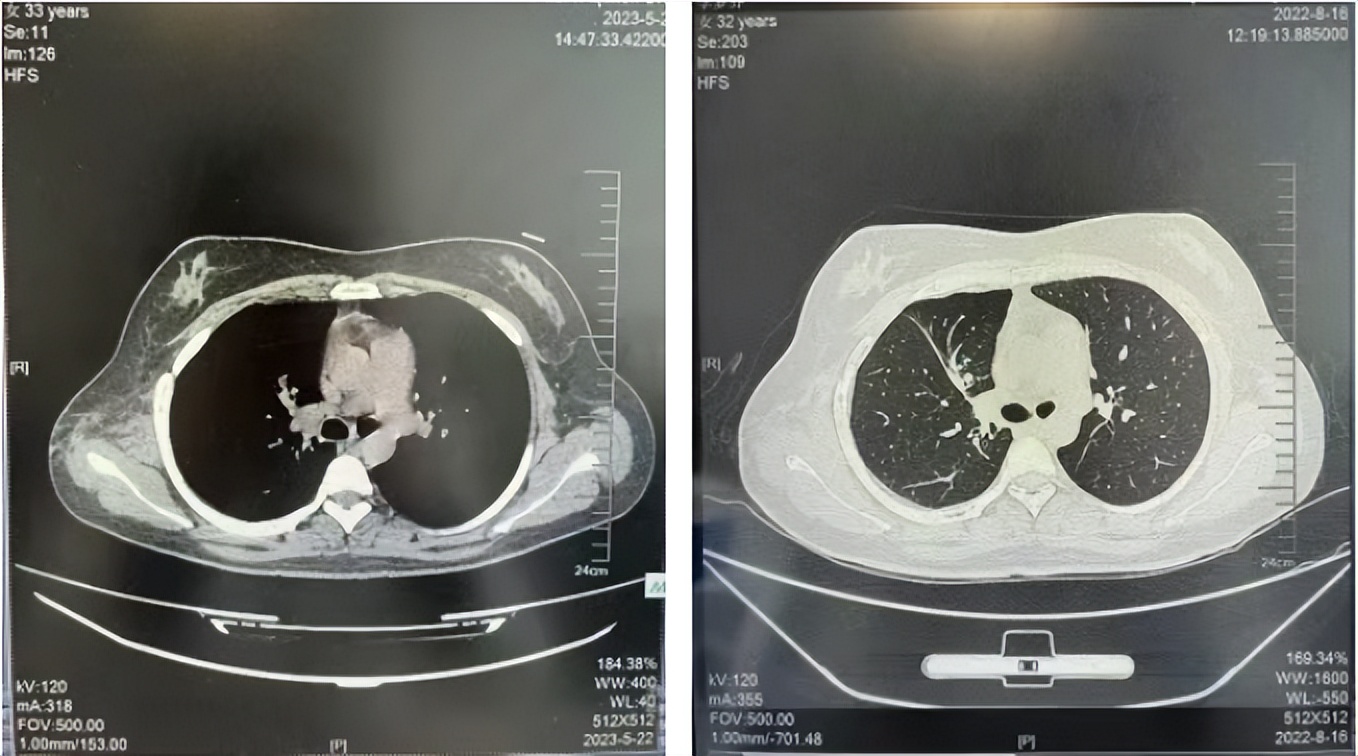

2016年1月复查CT提示支气管截断可见新发小结节,一线治疗采用培美曲塞+DDP方案化疗4周期(培美曲塞3.36,DDP 480mg)。化疗后复查胸部CT:右肺见不规则结节样影,最大层面大小约19mm*8mm,较前比较明显增大,疗效评估PD。2017.3-2017.4予单药多西他赛化疗3周期,疗效评估SD。2018年5月末复查CT提示结节较前增大,评效为PD,2018年6-10月予多西他赛+CBP化疗4周期,疗效评估SD。2022年5月患者出现活动后气短,复查胸部CT示右肺膨胀不良;右侧胸腔积液增多。胸腔积液包埋病理示符合肺腺癌细胞。行NGS基因检测:EML4:exon13-ALK:exon20融合。PD-L1(克隆号22C3)TPS<1%。

临床诊断:右肺上叶恶性肿瘤rT0N0M1a IVA期(第9版分期);恶性胸腔积液。

诊疗经过:2022年5月始口服克唑替尼3个月,出现肝功能异常(DILI 2级伴临床症状),改用恩沙替尼靶向治疗至今,目前评效为维持PR。恩沙替尼应用期间出现轻度肝功能异常(DILI 1级),对症处理后好转。截止目前PFS 33个月。

2022.05

2022.08

2023.05